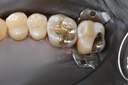

Alan Chinn #2 & 5 amalgam removal